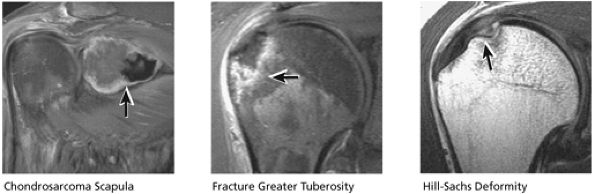

FIGURE 8.40 Acromioclavicular Joint.

FIGURE 8.41 Subscapularis and Biceps.

FIGURE 8.42 Labrum.

FIGURE 8.43 Capsule.

FIGURE 8.44 Glenohumeral Joint Cartilage.

FIGURE 8.45 Osseous.

FIGURE 8.46 Rotator Cuff.

FIGURE 8.47 Muscle.

FIGURE 8.48 Rotator Cuff.

FIGURE 8.49 AC Joint.

FIGURE 8.50 Acromion.

FIGURE 8.51 Biceps Tendon.

FIGURE 8.52 CHL and SGL.

FIGURE 8.53 Glenoid Fossa.

FIGURE 8.54 MGL and IGL.

FIGURE 8.55 Sample Case.